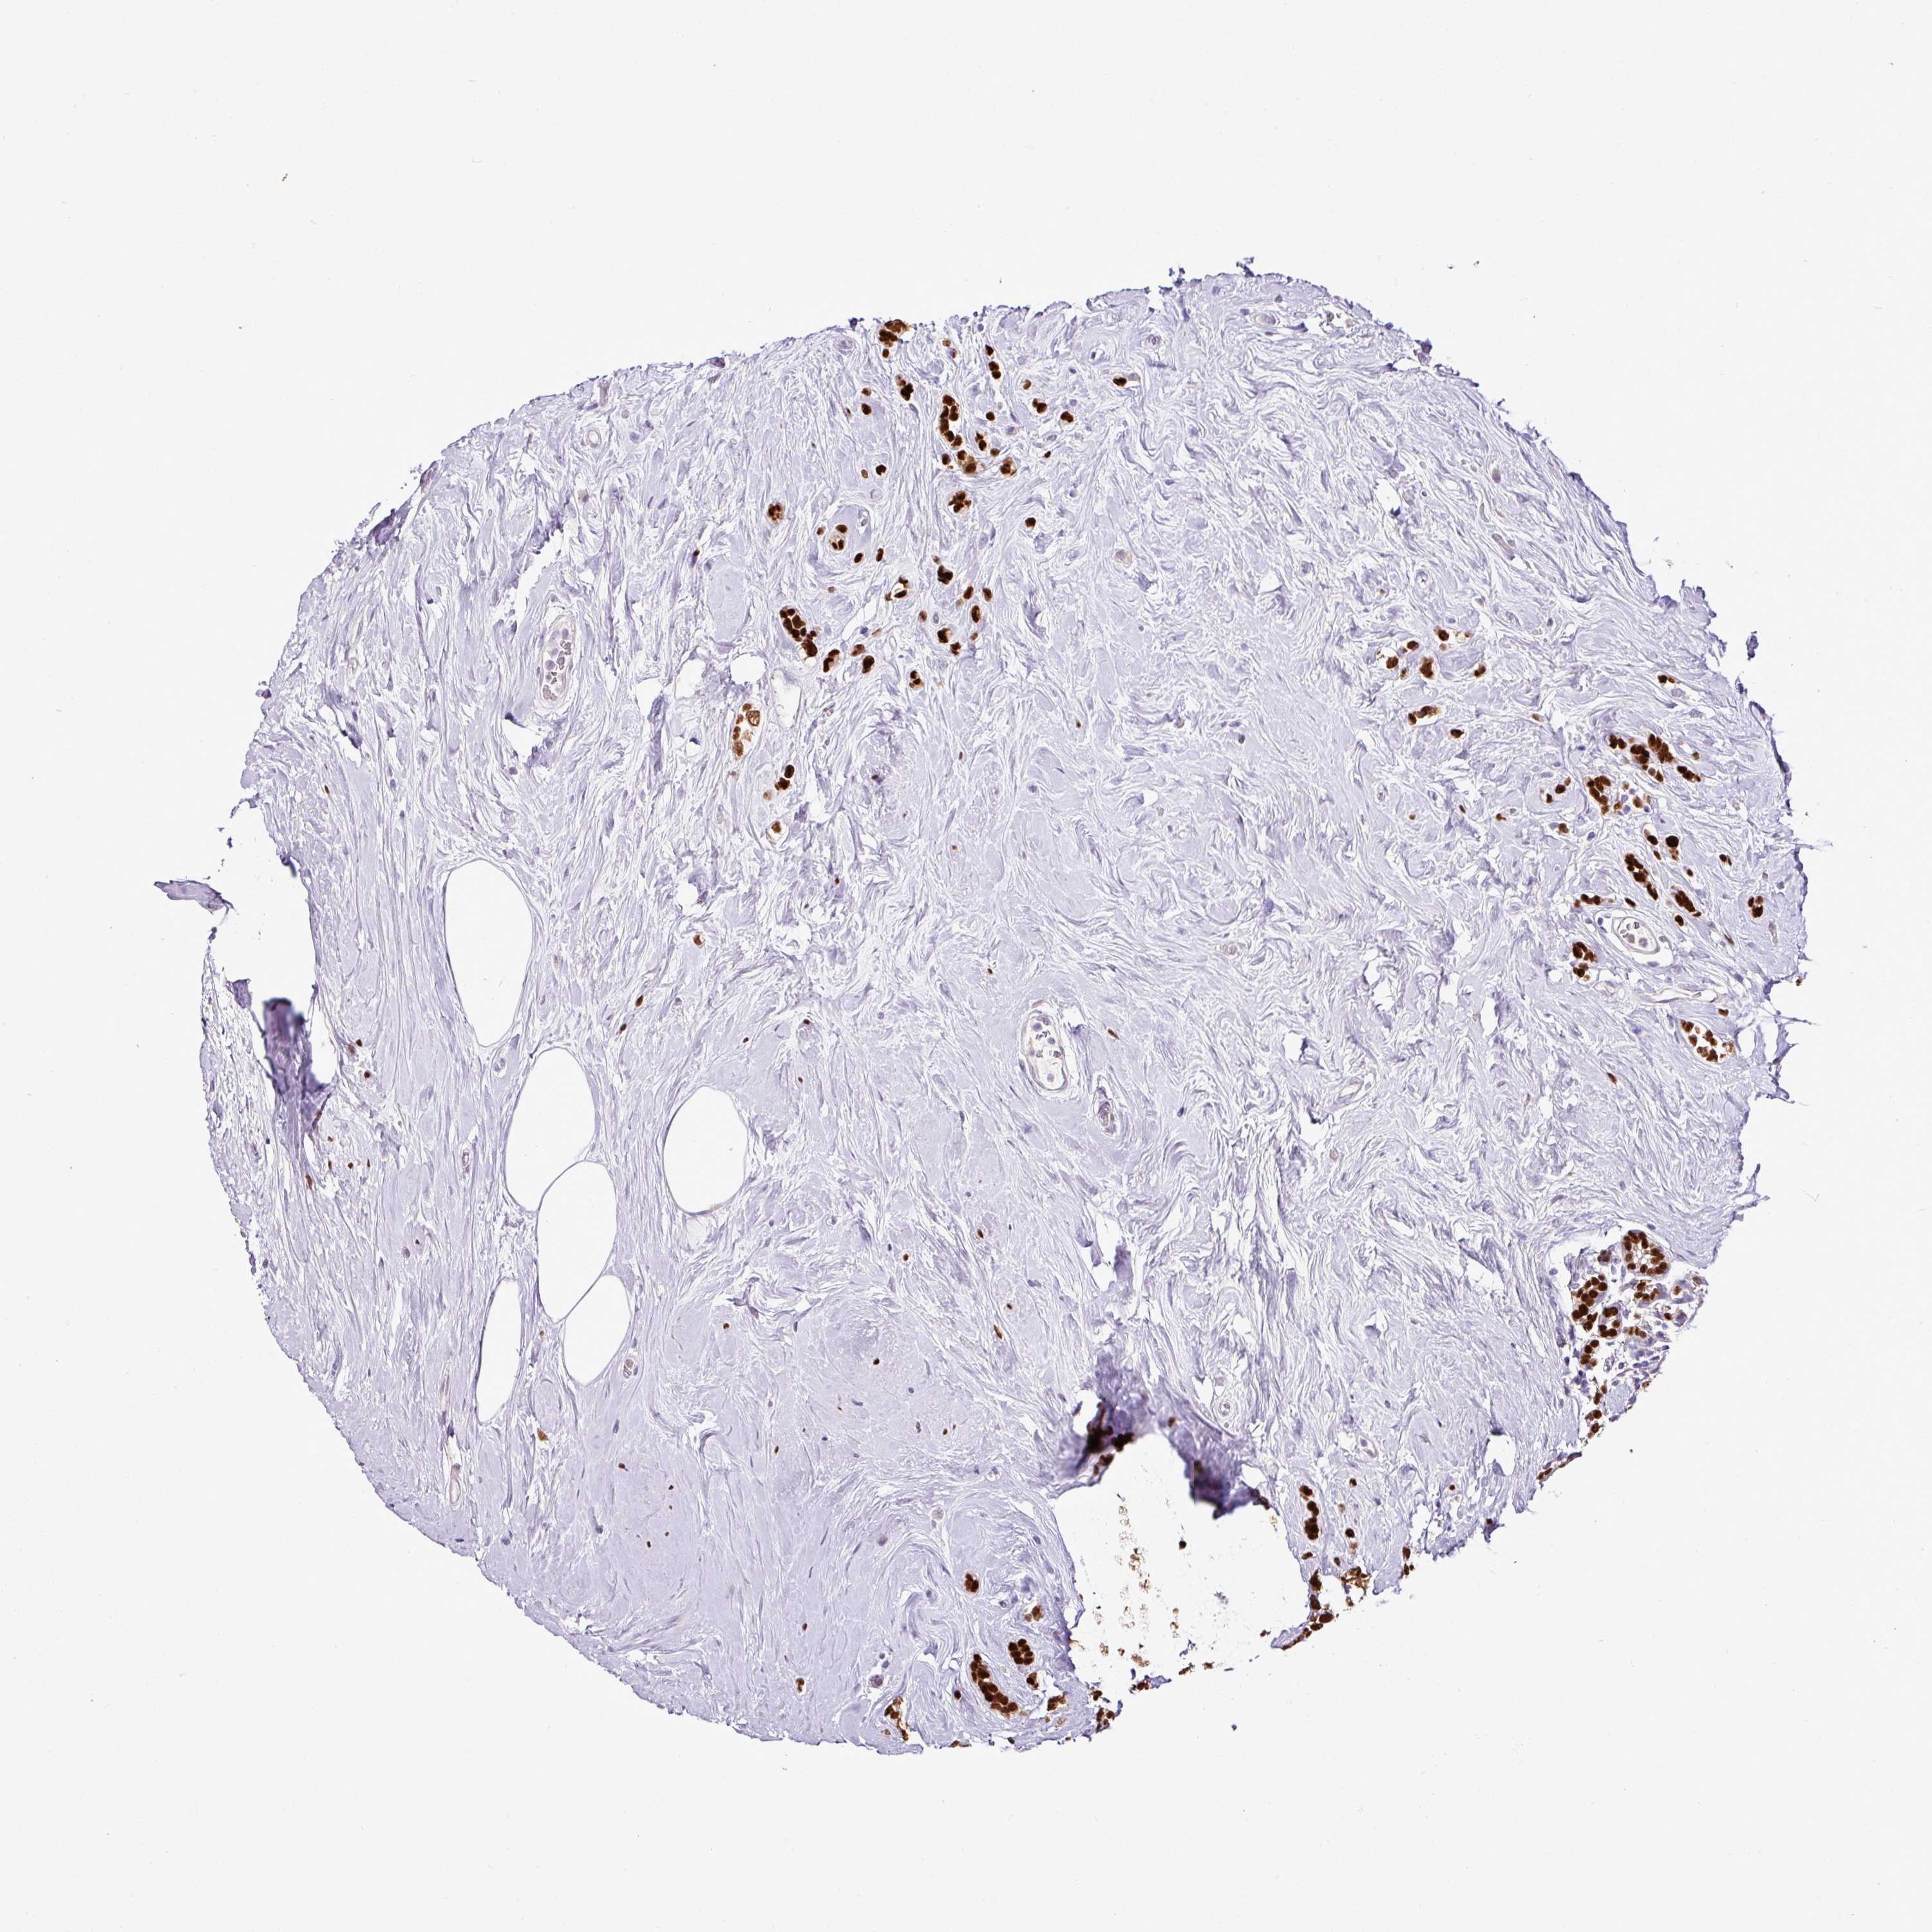

Breast cancer

Human cancer